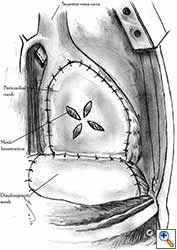

Pericardioplasty is also indicated for pericardial defects resulted after harvesting the pericardium to cover the bronchial stump after pneumonectomy (Figures 2a, 2b) [3]. Similarly, other defects that result after harvesting a pericardial graft for various purposes may need prophylactic reconstruction.

The pleural flap is easy to harvest but is not a strong material. Pedicled pericardial fat is frequently used to cover the bronchial stump after pneumonectomy and simultaneously for pericardioplasty. Because it is not a strong material, cardiac herniation after pericardial reconstruction with mediastinal vascularized fat pad has been reported [3]. Fascia lata is efficient in terms of its strength, but using it requires anticipation of the pericardial reconstruction and the preparation of an additional operative field and an additional incision in the thigh region [1-3]. Pericardial reconstruction using a diaphragmatic patch (Figures 6a, 6b) requires careful harvesting of the graft to preserve its vascularisation from the phrenic arterial neurovascular trunk. The site of the diaphragmatic resection must be closed after reconstruction. The diaphragmatic patch is strong and elastic and it can also be used to cover the bronchial stump after pneumonectomy or to wrap the tracheo-bronchial anastomosis after sleeve pneumonectomy. Another potential advantage is the plication of the diaphragm at the site of its resection, which can prevent postoperative paradoxical diaphragmatic movement in patients with phrenic nerve resection for tumor involvement [8]. The main advantage of using autologous materials in pericardial reconstructions is that the material is well tolerated, resistant to infection, and free of cost.